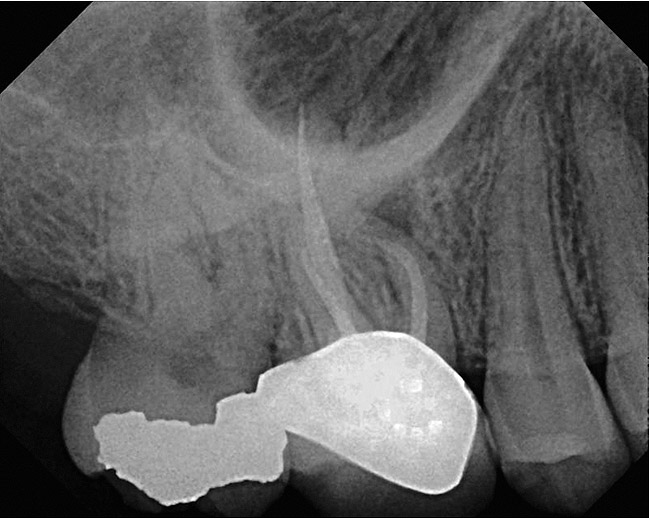

A 42-year-old woman presents for emergency treatment with a chief complaint of severe pain over the past 2 days in her upper jaw. The patient attributes the pain to tooth No. 3, as it received endodontic therapy 2 years ago (Figure 1). She complains of severe (pain score of 9/10), dull, throbbing pain in the right side of the face, jaws, and cheek that radiates into the temple with episodes of acute sharp pain, which is more severe at night, and appears to be stemming from the maxillary right molar (tooth No. 3). The patient has been awakened with pain over the past couple of nights and takes 600 mg of ibuprofen for relief. The patient also complains of a history of cold sensitivity from that tooth over the past couple of months and a history of low-grade chewing pain ever since the root canal. The past dental history is significant for a recent prophylaxis and fluoride treatment within the past month, and two fillings in the maxillary left side (teeth Nos. 12 and 14), and a crown in tooth No. 30 within the past 3 months (Figure 2). The patient’s medical history is insignificant, with no allergies reported. Extraoral tests are insignificant for objective findings. Intraoral tests show that tooth No. 3 is sensitive to percussion (3/10) and the radiograph shows a localized periapical radiolucency associated with the mesiobuccal (MB) root of this tooth.

At this point, a diagnosis of previous endodontic therapy with a failing MB root in tooth No. 3 appears clear. But whether the cause of the patient’s chief complaint is this pathology or not requires further investigation. Because the patient complains of severe pain and increasing thermal sensitivity over the past few weeks, testing should be directed toward a diagnosis of a degenerating vital pulp and not a tooth with a history of endodontic treatment. Necrotic teeth or failing endodontically treated teeth do not manifest thermal sensitivity. This is why clinical tests, in combination with an emphasis on duplicating the patient’s chief complaint, are necessary to arrive at the correct diagnosis. After clinical tests are performed, tooth No. 30 is found to a have a severe, lingering response to the cold test and is slightly “different” to percussion. This test duplicates the patient’s chief complaint. Endodontic therapy in this tooth is performed and pain is relieved (Figure 3). Tooth No. 3, with its apical pathology around the MB root, is later retreated to address a missed second mesiobuccal canal (MB2), relieving the patient from the chewing pain (Figure 4).

Figure 2  Preoperative view of tooth No. 30.

Figure 2

Figure 3  Postoperative view of tooth No. 30.

Figure 3